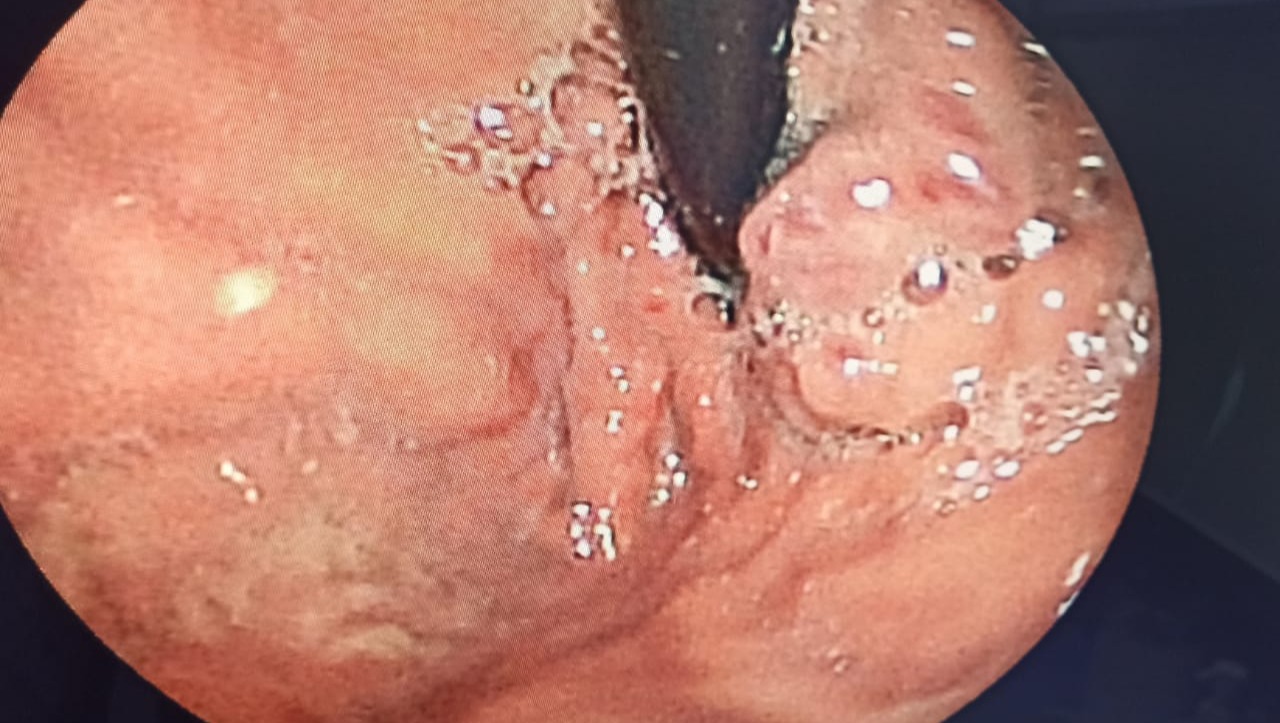

- Varices esofágicas III, IV y V de Degradi

- Varices gástricas Gov I y Gov II

- Degradi's III, IV and V esophageal varices

- Gastric varicose veins Gov I and Gov II